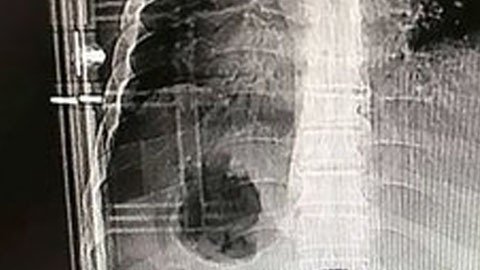

La barra entró en su cuerpo a través de su parte trasera. Las imágenes de rayos X muestran cuán profundamente se clavó el metal dentro de su torso.

El trabajador, que prefirió permanecer en el anonimato, tuvo mucha suerte. Aunque se clavó la barra bien adentro, no dañó ningún órgano y consiguió, por poco, evitar el contacto con su columna vertebral.